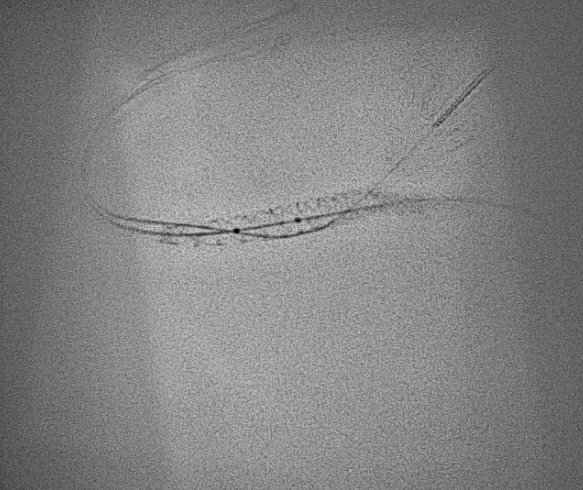

PCI was performed with a 7Fr JR4 Guide with wires in the RPDA and RPL. Lesion was predilated and stented with a 2.75x33m DES and postdilated with a 4.5mm NC proximal to the RCA bifurcation. IVUS showed underexpansion distally and severe malapposition proximally hence the stent was further postdilated with 2.75mm NC distally and 4.5mm in the distal RCA. ClearStent showed unravelling of the stent, which was confirmed on IVUS with a new total stent length of 52mm. The distal RCA diameter had grown in size to 5mm at the site of the proximal stent edge. A 4.5x24mm DES was implanted in the distal RCA to cover the unravelled stent struts, which was postdilated with a 5mm NC balloon. Final IVUS showed the stent to have adequate apposition with no immediate complications.

Case Summary